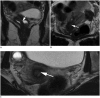

Magnetic resonance imaging is the optimal modality for pelvic imaging. It is based on T2-weighted magnetic resonance (MR) sequences allowing uterine and vaginal cavity assessment as well as rectal evaluation. Anatomical depiction of these structures may benefit from distension, and conditions either developing inside the lumen of cavities or coming from the outside may then be better delineated and localized. The need for distension, either rectal or vaginal, and the way to conduct it are matters of debate, depending on indication for which the MR examination is being conducted. In this review, we discuss advantages and potential drawbacks of this technique, based on literature and our experience, in the evaluation of various gynecological and rectal diseases.